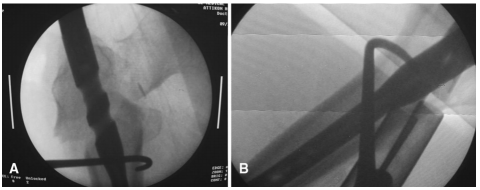

球钉推进器、骨钩或Hohmann拉钩等器械可用于直接复位骨折,方法是在骨折处作辅助切口,并钝化剥离骨折部位的筋膜。必须战略性地选择器械的位置,以便进行适当的节段处理(如图3a-c所示)。如果使用球钉,建议用2.7mm钻头在骨头上打一个小的单皮质孔,以避免器械滑动和移位。在典型的股骨粗隆下骨折中,远端骨折是内收的,用骨钩进行外侧牵引远端骨折块可能有助于复位。在这种特殊的情况下,需要一个大约3~4厘米的辅助切口,钩子应该从后面通过到远端骨折的内侧。然后,外科医生可以外展并抬高远端片段,以实现骨折充分复位和导丝的通过(如图4A,B所示)。类似地,可以用骨钩复位近端骨折,然后用复位骨夹固定(如图5a-c所示)。对于复杂粉碎性骨折,通过同一切口,可以用柯克氏钳操作骨折块(如图6A,b所示)。

图3 A(正位)和B(侧位)C臂机透视下显示使用Hohmann牵引器进行股骨粗隆间骨折微创复位;C在整个手术过程中,Hohmann牵引器一直固定在适当的位置

图4 A(正位)和B(侧位)C臂机透视下显示使用骨钩进行股骨粗隆间骨折微创复位